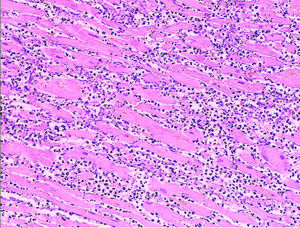

Histopathological examination of the heart may reveal infarction at autopsy. Under the microscope, myocardial infarction presents as a circumscribed area of ischemic, coagulative necrosis (cell death). On gross examination, the infarct is not identifiable within the first 12 hours.

Although earlier changes can be discerned using electron microscopy, one of the earliest changes under a normal microscope are so-called wavy fibers. Subsequently, the myocyte cytoplasm becomes more eosinophilic (pink) and the cells lose their transversal striations, with typical changes and eventually loss of the cell nucleus. The interstitium at the margin of the infarcted area is initially infiltrated with neutrophils, then with lymphocytes and macrophages, who phagocytose ("eat") the myocyte debris. The necrotic area is surrounded and progressively invaded by granulation tissue, which will replace the infarct with a fibrous ( collagenous) scar (which are typical steps in wound healing). The interstitial space (the space between cells outside of blood vessels) may be infiltrated with red blood cells.

These features can be recognized in cases where the perfusion was not restored; reperfused infarcts can have other hallmarks, such as contraction band necrosis.